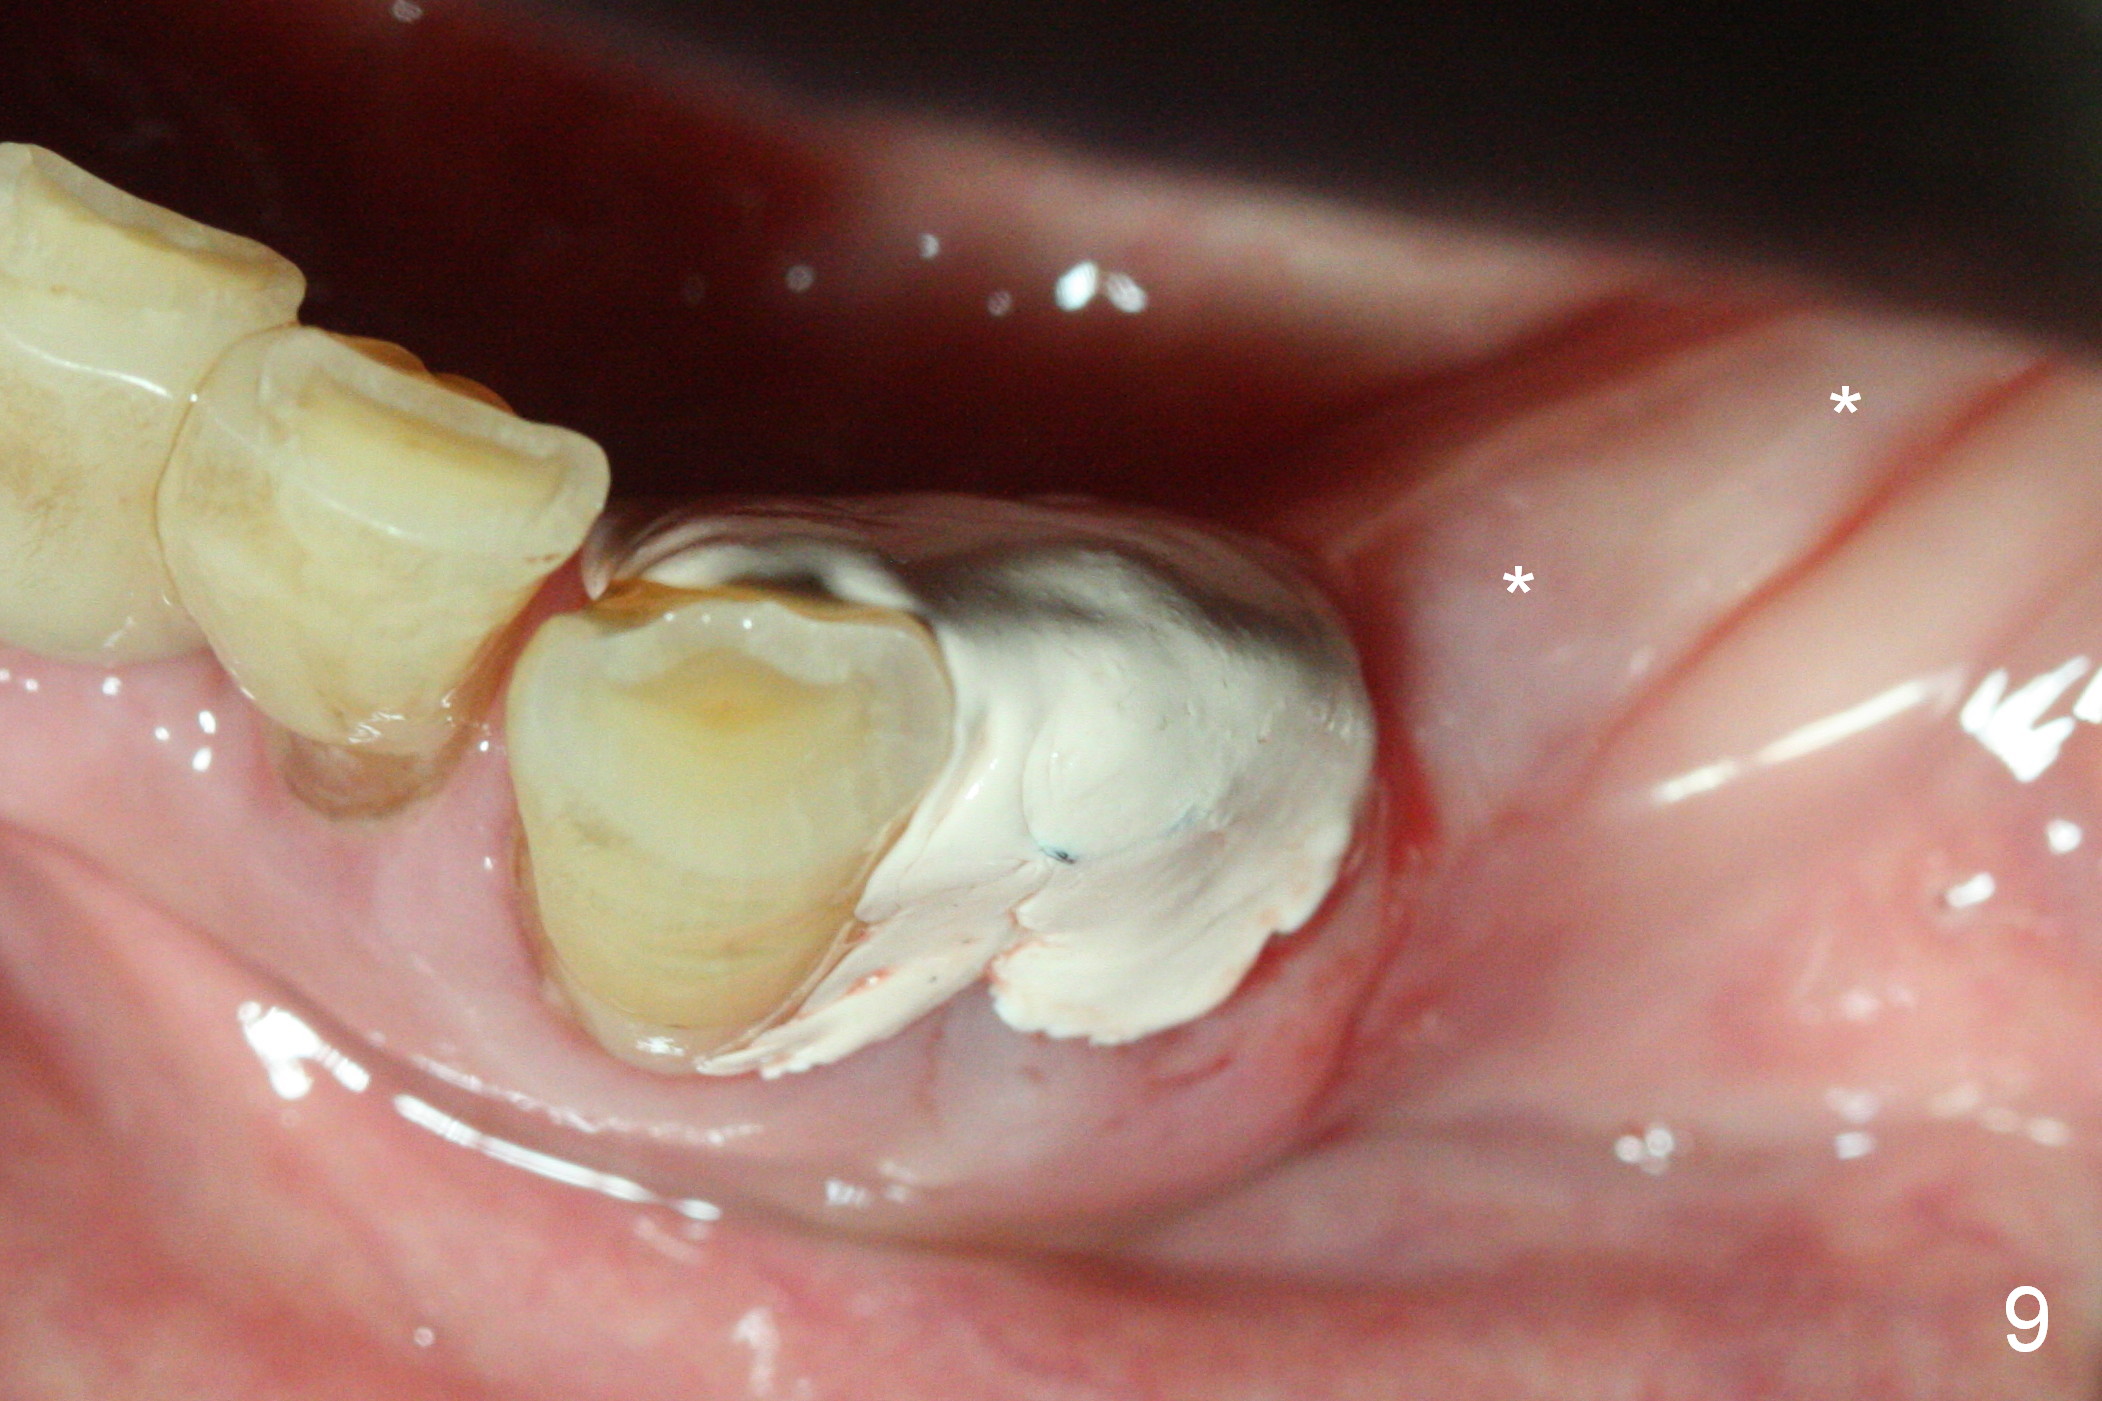

A 72-year-old man presents to clinic for implants because of pain associated with wearing the lower partial. The teeth #21, 24, 25 and 31 seem to be non-salvageable and are going to be replaced by implants so that the lower RPD can be reused (Fig.1). The edentulous ridge is atrophic (Fig.9 *). The upper complete denture appears to be functional. Since the tooth #21 is symptomatic (Fig.2) and the patient has chronic TMJ dislocation, the affected tooth is extracted first (Without antibiotic socket treatment) for immediate implant (Fig.3 (1.5 mm drill (placed more lingually)). The lower RPD is used as a surgical guide (Fig.4 (3 mm drill in place)). When a 3.8x16 mm implant is placed with bone graft (Fig.5 *), the underlying neurovascular bundle is undetected. A small field of panoramic X-ray is retaken; it seems that there is enough clearance from the Mental Foramen (Fig.2,6,7 (red dashed line)) and the Incisive Canal (pink dashed line). The implant is then placed 2 mm more apically (Fig.7) to reduce the chance of periimplantitis since the buccal plate is lost. A 5.5x5(5) mm abutment is placed (Fig.5) with more graft. The access of the abutment is left open so that a part of periodontal dressing is inserted for additional retention (Fig.8,9). The RPD is placed back for adaptation of the dressing. The patient is advised not to wear the RPD postop to reduce micromovement.